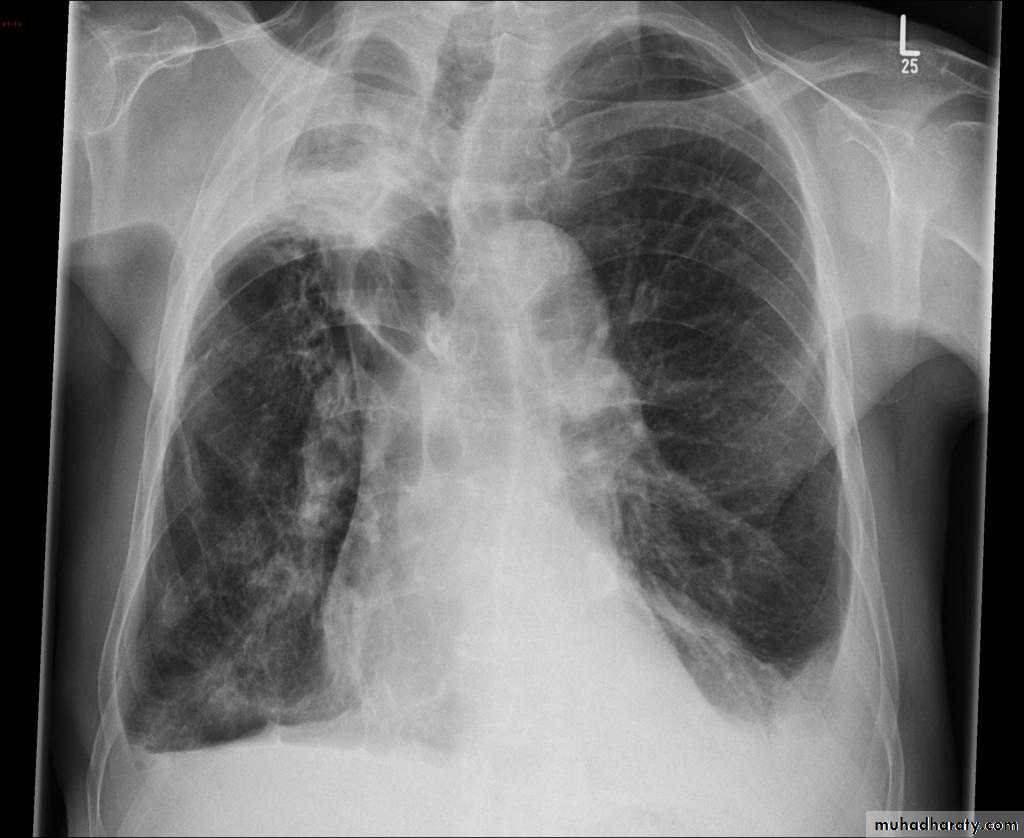

Left upper lobe collapse has distinctive features but can be challenging to identify on chest radiographs by the uninitiated.

Radiographic features

The left upper lobe collapses anteriorly becoming a thin sheet of tissue apposed to the anterior chest wall, and appears as a hazy or veiling opacity extending out from the hilum and fading out inferiorly . It thus reverses the normal slight increase in radiographic density seen as you move down the lung (due to increased thickness of the chest soft tissues).

Parts of the normal cardiomediastinal contour may also be obliterated where the left upper lobe, particularly the lingula abut the left heart border. The anterior parts of the aortic arch are also often obliterated from view.

In some cases the hyperexpanded superior segment of the left lower lobe insinuates itself between the left upper lobe and the superior mediastinum, sharply silhouetting the aortic arch and resulting in a lucency medially. This is known as the luftsichel sign.

The left hilum is also drawn upwards, resulting in an almost horizontal course of the left main bronchus and vertical course of the left lower lobe bronchus.

Non-specific signs indicating left sided atelectasis will also be present, including:

elevation of the hemidiaphragm

'peaked' or 'tented' hemidiaphragm: juxtaphrenic peak sign

crowding of the left sided ribs

shift of the mediastinum to the left

On lateral projections the left lower lobe is hyperexpanded and the oblique fissure displaced anteriorly. There is associated increase in the retrosternal opacity.